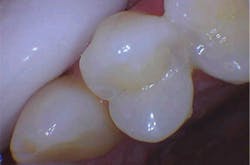

With the help of magnification, we are able to prepare small Class II lesions without sacrificing the marginal ridge, ensuring the longevity of our restoration and maximizing the remaining tooth structure with this minimally invasive approach (figures 3a–3d).

Figures 3a–3d: Minimally invasive Class II preparation with marginal ridge preservation